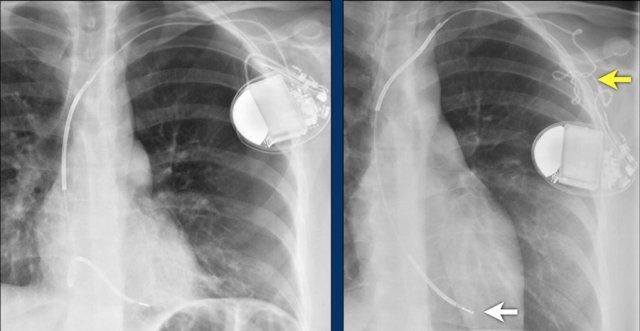

Hình ảnh bên trái cho thấy bệnh nhân có ICD được đặt đúng vị trí.

Vài tháng sau, thiết bị hoạt động không bình thường do hộp ICD và điện cực bị xoay (mũi tên vàng) và co rút lại (mũi tên trắng).

Đây là một bệnh nhân khác mắc hội chứng Twiddler.

Lưu ý hình ảnh điện cực bị cuộn xoắn gần máy tạo nhịp và tại đầu điện cực trong thất phải (mũi tên).